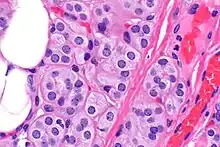

| Microscopic image of a thyroid adenolipoma | |

Adenolipomas are diagnosed by surgical resection and examining the tumor with a microscope.[5] The presence of eccrine sweat glands are used to distinguish the tumor from a common lipoma. Size and the development of the capsule (tissue surrounding the tumor) can also aid in diagnosis. [6]